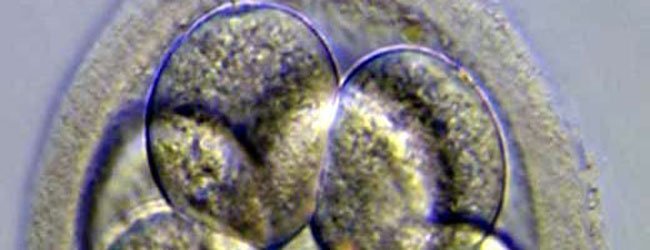

Es un incubador que permite observar en todo momento, como si fuera un cine, el momento exacto de división y el consumo de oxígeno del embrión, dos variables necesarias para determinar cuál de ellos es el más viable para garantizar el éxito de la fecundación. La gran ventaja del método es que, a diferencia del tradicional, no hay necesidad de manipular los embriones y exponerlos a los cambios de luz y temperatura que podrían alterar su desarrollo.

Está sacando fotografía constantemente cada 10 o 15 minutos que luego se comprimen en una película para conocer el momento exacto de la división celular, que debería darse entre las 25 y las 30 horas posteriores a la fecundación.